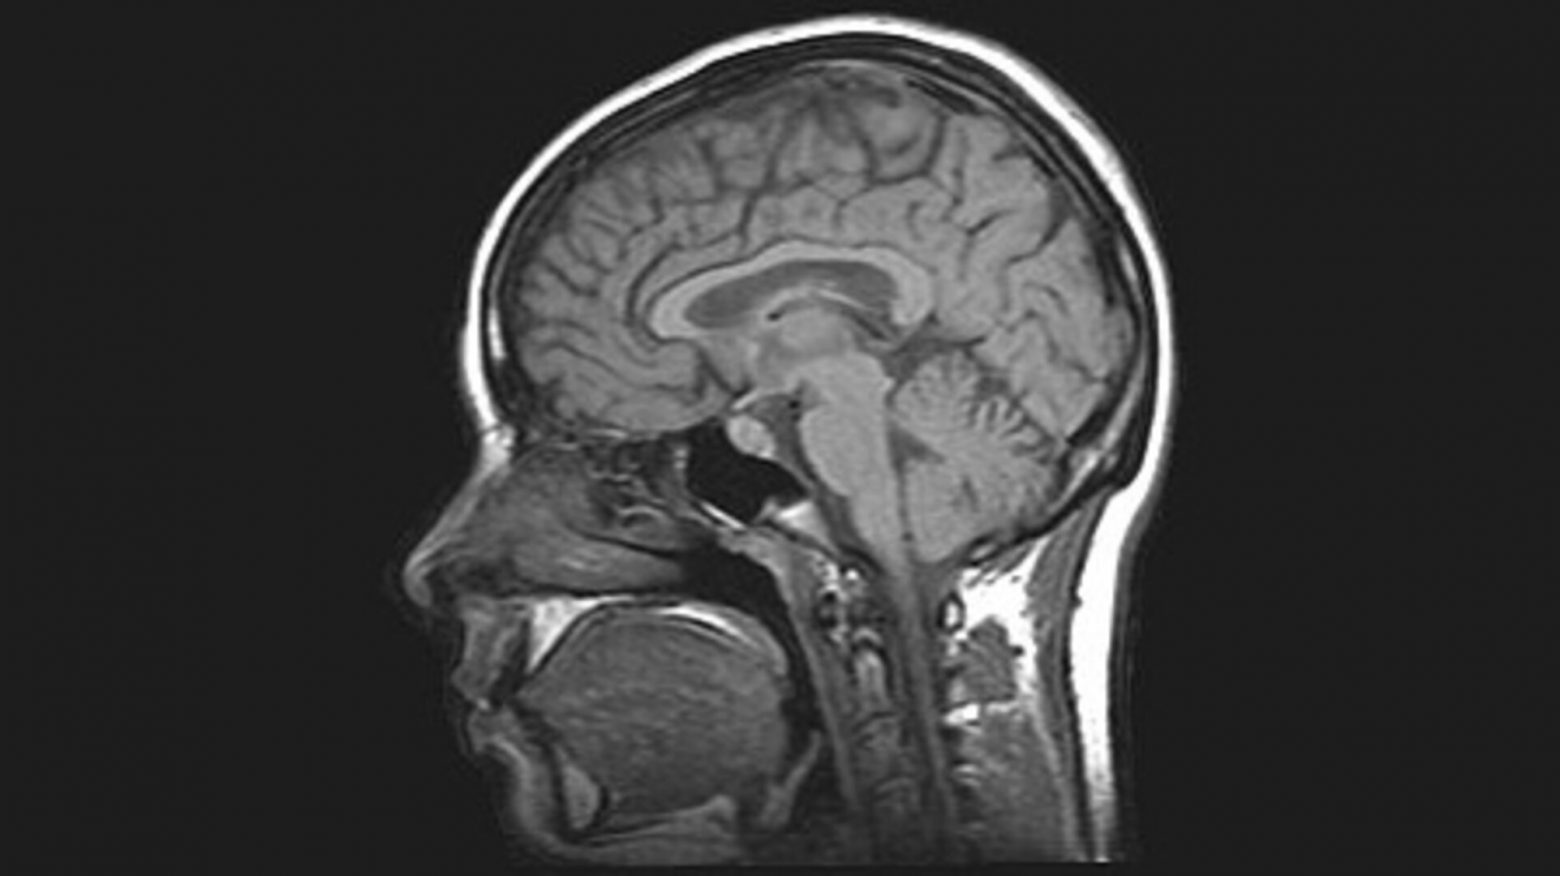

Μια νέα παραλλαγή της μαγνητικής τομογραφίας, ικανή να παρακολουθεί τους ιστούς σε τρεις διαστάσεις και σε πραγματικό χρόνο, αποκαλύπτει πώς ο εγκέφαλος πηγαινοέρχεται μέσα στο κρανίο με κάθε σφυγμό.

Η απότομη αύξηση της πίεσης του αίματος με κάθε καρδιακό παλμό αναγκάζει τον εγκέφαλο να πάλλεται αιωρούμενος μέσα στο εγκεφαλονωτιαίο υγρό που προστατεύει το κεντρικό νευρικό σύστημα.

Η νέα μέθοδος ονομάστηκε «ενισχυμένη μαγνητική τομογραφία τριών διαστάσεων (3D aMRI) ακριβώς επειδή «ενισχύει», ή μεγεθύνει, τις κινήσεις των ιστών.